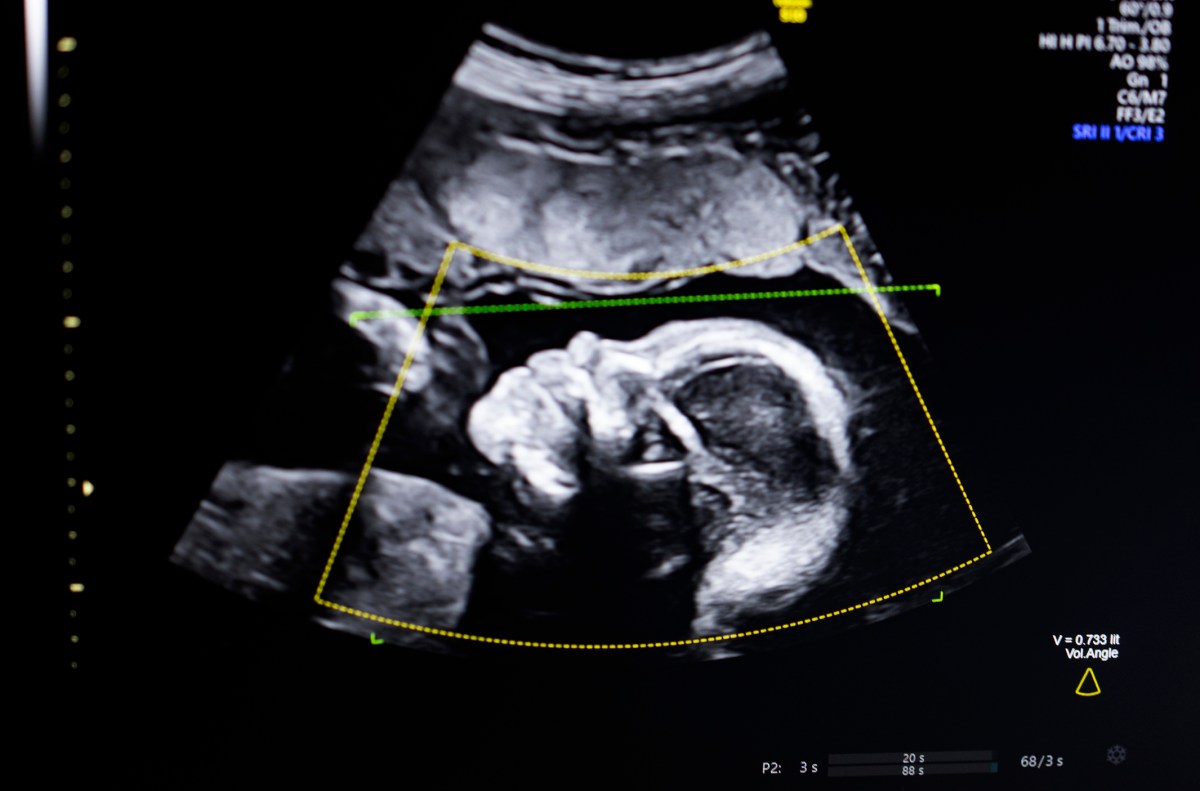

The technology uses computer vision AI to “support fetal ultrasound quality assessment, anatomical integrity, automated reporting, and seamless integration into clinical workflows,” Bustami told TechCrunch.

Bustami said prenatal ultrasounds are the “cornerstone” of pregnancy monitoring, but poor image quality can lead to misdiagnoses.